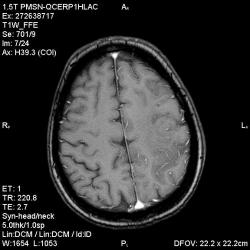

Из анамнеза - Женщина 45 лет. За год похудела на 15 кг (со слов матери), в последние месяцы случались эпизоды потери сознания. Онкозаболеваний и прочая в анамнезе нет. Сознание спутанное, из особенностей в анализах только подъем амилазы крови.

К сожалению, не владею методом КТ, но учитывая наличие неравномерного уплотнения в мозговых структурах с элементами очаговых "вкраплений", единственное, что приходит на ум - это рассеяный склероз. Хотелось бы уточнить, что беспокоило пациентку в течение последнего года кроме потери веса и эпизодов потери сознания? Была ли какая-либо очаговая неврологическая симптоматика? Отмечались ли какие-либо расстройства в двигательной или чувствительной сфере и т.д.? С уважением Helenmar.

И это точно не РС, т.к. характер очагов другой, ни один из них не копит контраст, нет субтенториальных очагов (извиняюсь, я этого в сообщении не указал), нет клиники.

"Раскрою" карты. Мы подумали о синдроме MELAS (mitochondrial encephalomyopathy, lactic acidosis and stroke) - дословно, митохондриальная энцефаломиелопатия, лактоацидоз и инсульт. В качестве дифференциальной диагностики можно было бы предположить вирусный энцефалит, но опять-таки, расположение очагов смущает - только с одной стороны и в абсолютно различных структурах.

В данном случае мы видим импульную последовательность FLAIR - режим с подавлением сигнала от воды, поэтому ликвор гипоинтенсивен, а также (вторая серия) - изображения, взвешенные по T1 после введения контрастного препарата. На T1 жидкость (ликвор) также представляется гипоинтенсивной. Зато на этих сериях гиперинтенсивны сосуды, т.к. контрастное вещество циркулирует в кровяном русле.

Что касается "белых" костей свода черепа, так это не кости, а кожа и подкожная клетчатка. Кости - глубже, "серовато-черные".

Изменения носят сосудистый характер. Процесс достаточно острый, имеется объемное воздействие, борозды левой гемисферы компремированы. По поводу MELAS синдрома очень сомневаюсь, почему поражена только левая гемисфера? Надо делать МР-ангиографию, смотреть нет ли стеноза

MELAS синдром - дебютирует с детских лет, характерен целый комплекс неврологических проявлений, заболевание генетическое, поражение системное, хотя есть множество вариантов митохондриального поражения, все же сомнительно. Хотелось бы акцентировать внимание, что гиперинтенсивные очаги есть в мозолистом теле, поражены выражено перивентрикулярные отделы, U -пути, белое вещество, поэтому так категорично демиелинизацию не вычеркивала бы из дифряда ( хотя тоже нетипично односторонее поражение). Думаю, для объективных выводов все же мало общей информации о пациентке, были ли клинические эпизоды раньше, чем объяснить такую потерю веса (возможно есть проявление паранеопластического синдрома?). Ну и МРТ-контроль в динамике, ангиография.

Да, неоднозначный случай. Точно не РС и не ОНМК. Я бы написала асимметричную лейкоэнцефалопатию неясного генеза. Можно было бы думать о лимфоме (полифокальное поражение, да еще мозолистое тело вроде бы задействовано (эх, сагиттальчики бы)). Но! Учитывая отсутствие накопления КВ.... Ну и надо исключать интоксикацию, всяческие аутоиммунные процессы (в т.ч. и васкулиты), сахарный диабет, ну и естественно наследственную патологию обменных процессов. УУУх! Вот.......

Имхо ишемический онмк в бассейне сма. Особенно показательны 5-й и 6-й файлы, отграничение как раз на границе бассейнов средней и перикаллёзной. Плюс одностороннее поражение.